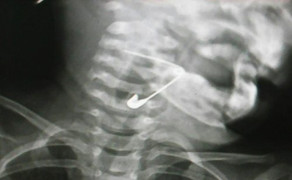

Theo gia đình bệnh nhi, trong lúc chơi đùa bé gái ở huyện Bình Giang, tỉnh Hải Dương đã vô tình nằm đè vào chiếc kim khâu.